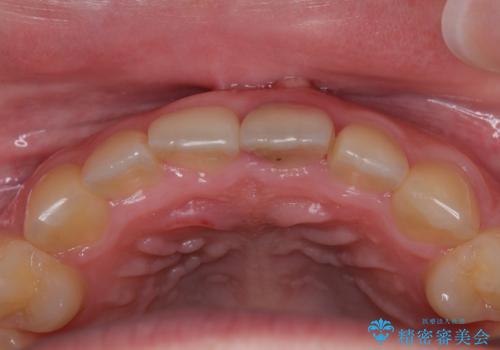

歯根吸収した前歯 短期間でのインプラント治療

- 前歯のインプラント治療を希望して来院された患者様です。

小学生の時に前歯を殴打したとのことで、歯根が吸収してしまい、抜歯が必要と判断されました。

抜歯、インプラント埋入、仮歯の装着が同時に可能な1DAYインプラントを行いたいところでしたが、吸収による歯肉の炎症が著しいため、抜歯後に炎症が治まるまで待機し、極力早期にインプラント埋入を行うこととしました。